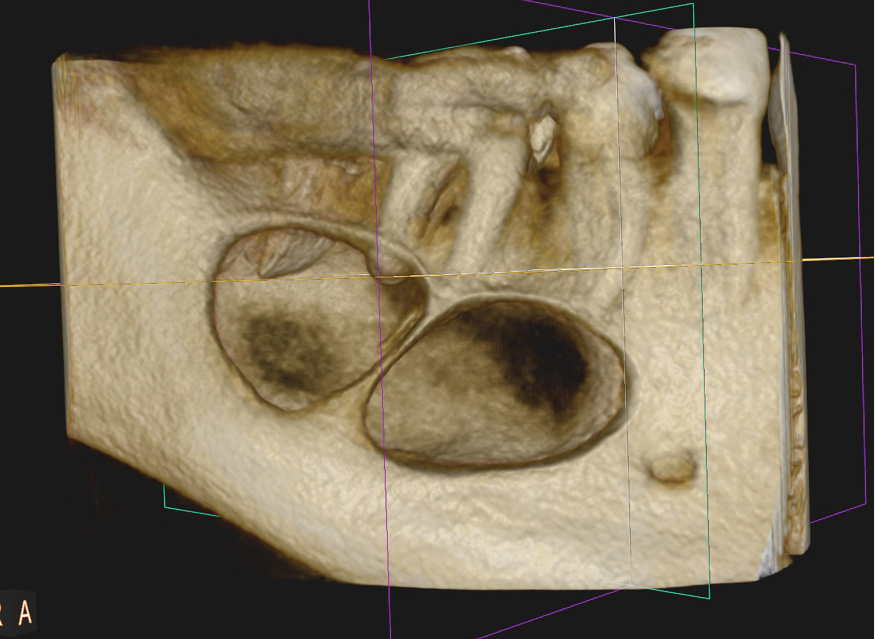

Streszczenie: W pracy przedstawiono dwa przypadki torbieli żuchwy o średnicy około 3 cm. Zastosowano leczenie jednoetapowe, podczas którego usunięto zmiany w całości wraz z przyczyną zębopochodną. Leczenie poprzez wyłuszczenie torbieli jest metodą z wyboru ze względu na zminimalizowanie ryzyka transformacji nowotworowej, możliwość oceny całego preparatu przez histopatologa oraz z powodu generowania najmniejszych niedogodności dla pacjenta. Diagnostyka z wykorzystaniem stożkowej tomografii komputerowej (CBCT) pozwoliła na ocenę wrażliwych struktur anatomicznych i zaplanowanie postępowania tak, aby zredukować ewentualne powikłania.

Summary: This paper presents two cases of mandible cysts with the diameter of approximately 3 cm. One-stage treatment was performed, during which the lesion was removed along with the affected teeth. Enucleation is a method of choice because it minimises the risk of cancer transformation, enables histopathological evaluation of the entire lesion and is the most comfortable for a patient. Diagnosis with the [...]